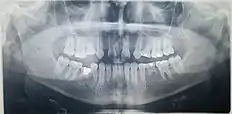

Galería de imágenes